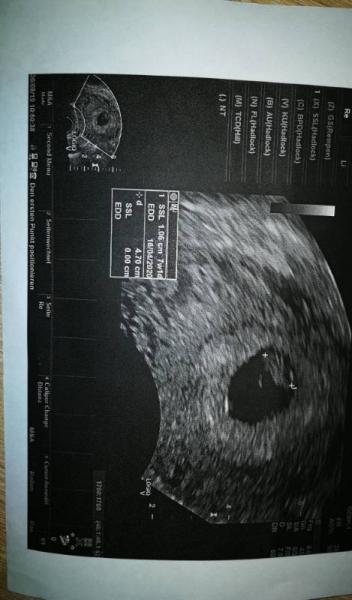

Ich bin so Happyes sieht alles gut aus, wie es sein sollte mit -Schlag...ich hatte so Angst vor schlechten Nachrichten und jetzt ist alles gut...

Bild zu Heute endlich den ersten Termin - Forum für April - Mamis